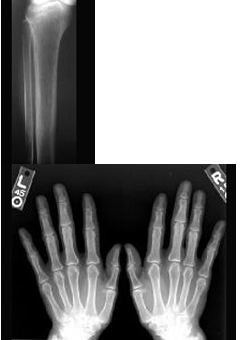

患者,男,60岁,糖尿病史20年,近半年来感双足趾端麻木。体检:消瘦,双手骨间肌萎缩,肌力Ⅳ级,病理反射阴性。下列哪项诊断可能性大( )

A:运动系统改变与糖尿病无关

B:糖尿病微血管病变

C:糖尿病自主神经病变

D:糖尿病并发脑血管意外

E:糖尿病周围神经病变